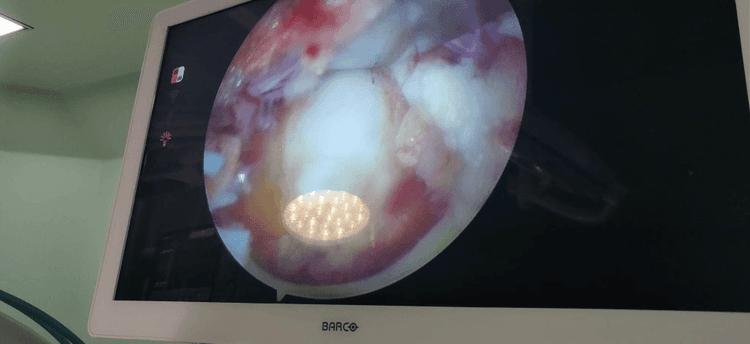

Unilateral biportal endoscopic (UBE) decompression technique is a percutaneous, full-endoscopic approach. Performed through two small incisions on either side of the spinous process, UBE allows freedom from the restrictions of working tubes or channels. With continuous high-pressure saline irrigation and a high-definition arthroscope, the surgeon can achieve precise decompression with a clear and magnified surgical field.

UBE endoscopy is an excellent alternative to microscopic-assisted minimally invasive surgery. Developed to improve muscle preservation and maintain surrounding normal anatomical structures, UBE has significant benefits over open spinal surgery.